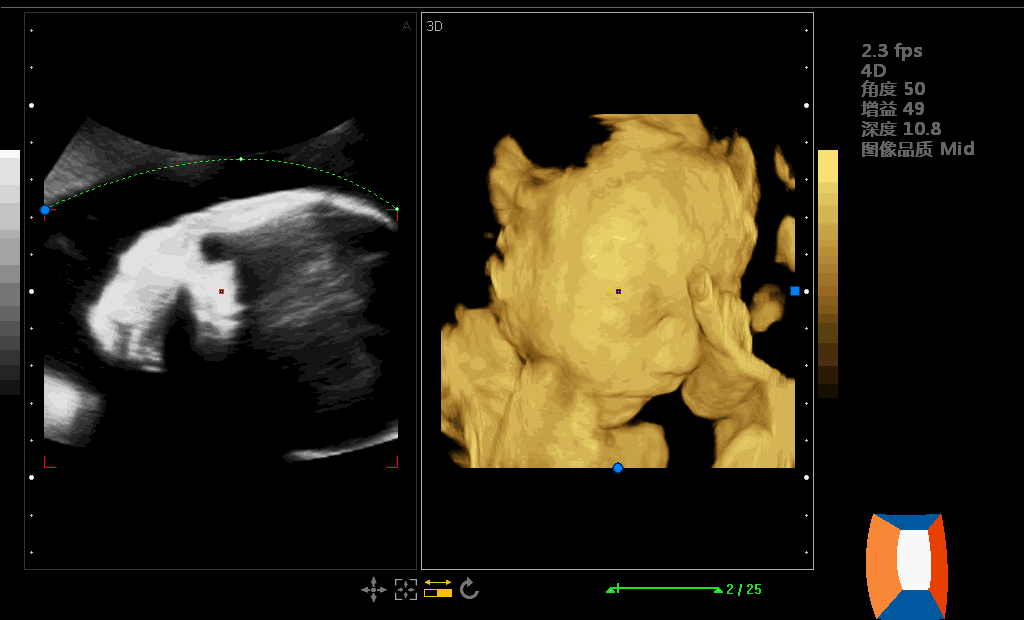

四维彩超是啥?

在专业领域上,四维多普勒超声是一种最大化直接了解到腹中婴儿身体状态的一种有效检查方式。

在对孕妇进行四维多普勒超声检查时,医护人员可以检查婴儿发育是否正常,包括器官是否发育正常,脸部特征和头部是否是正常。